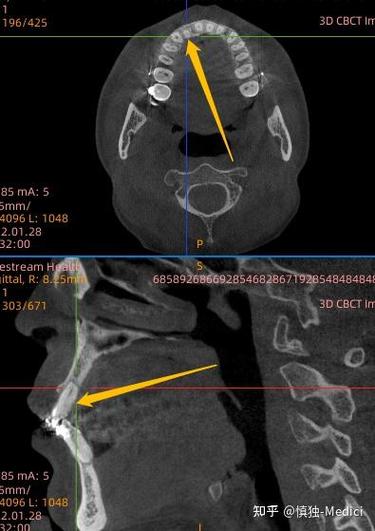

以深圳北大口腔某患者案例为例:25岁女性患者因牙齿拥挤选择该机构进行正畸,医生设计拔除四颗前磨牙的方案,治疗过程中患者多次反馈“咬合不适”,但医生解释为“正常调整期”,拆除矫治器后,患者发现牙齿中线偏移0.5cm,后牙咬合过紧,且出现颞下颌关节弹响疼痛,后续影像学检查显示,部分牙根吸收达1/3,牙槽骨厚度减少,与机构沟通时,对方称“个体差异”拒绝赔偿,患者不得不通过法律途径维权,耗时近两年才获得部分赔偿。

| 牙根吸收 | 牙根长度缩短、牙齿敏感 | 力度过大、治疗时间过长、个体易感性 |